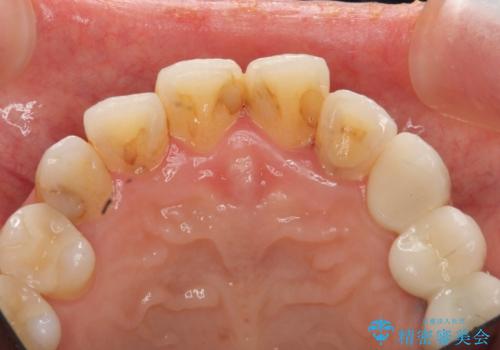

特に裏側のつぎはぎ、二次う蝕(治したところの境目からの虫歯)が多く、審美目的だけでなく、虫歯の治療としても意味があったと思います。

神経を温存するようにあまり削らないように治療しました。

また、色を決める前にホワイトニングを行い、全体的に歯を白くしてから色を決めました。